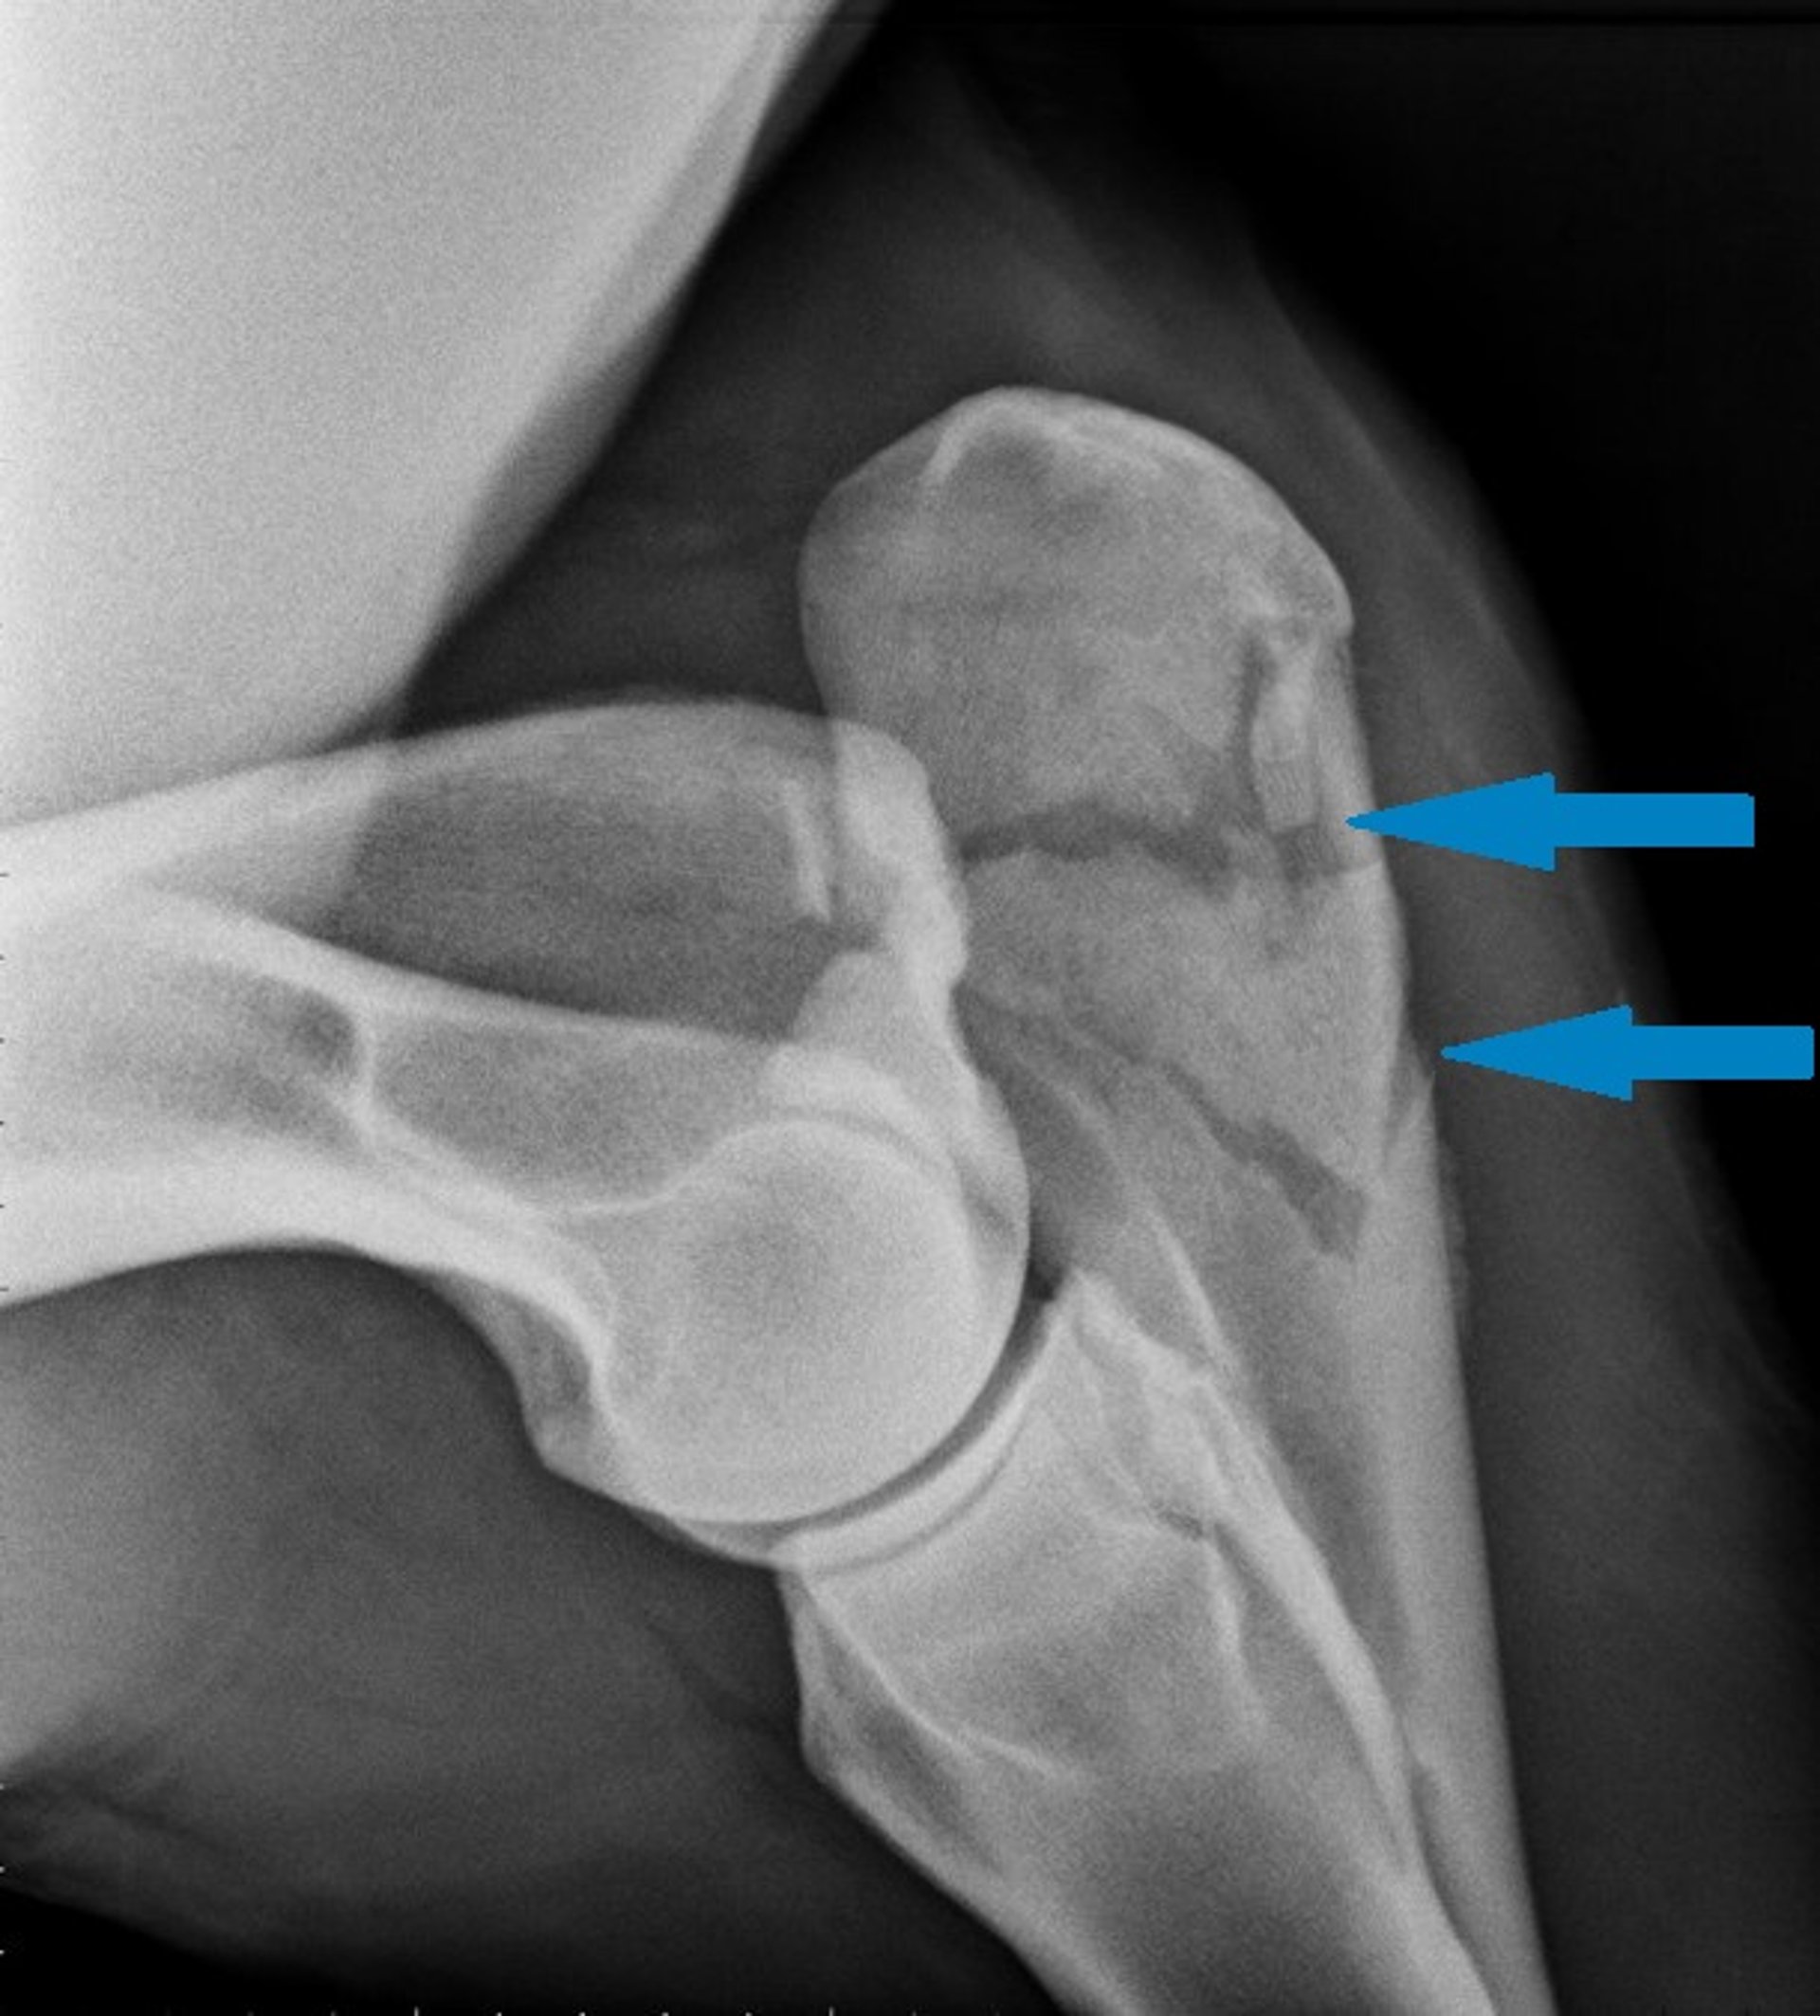

Imagen radiográfica que muestra una fractura cubital conminuta (flechas) en un caballo.

Cortesía de la Dra. Tracy A. Turner.